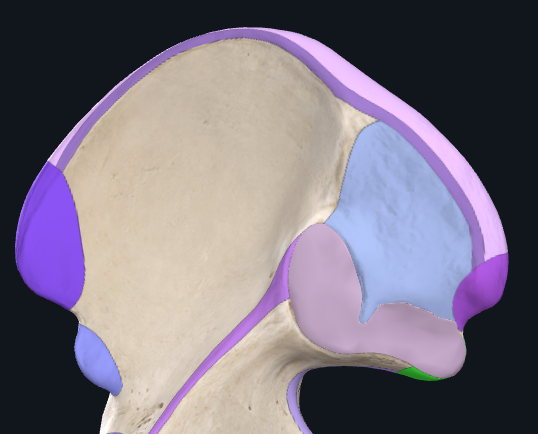

Acetabulum and femur - to form hip joint

These bones join at the tri-radiate cartilage that is found in the acetabulum. This cartilage fuses at around 15-17yo.